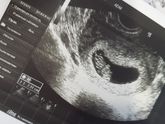

Наша бусинка, наша любовь, наше всё, вчера было ровно 9 недель нам? Как же я безумно люблю этого малыша?? Девочки, а вы когда забеременели почувствовали мальчик или девочка?)